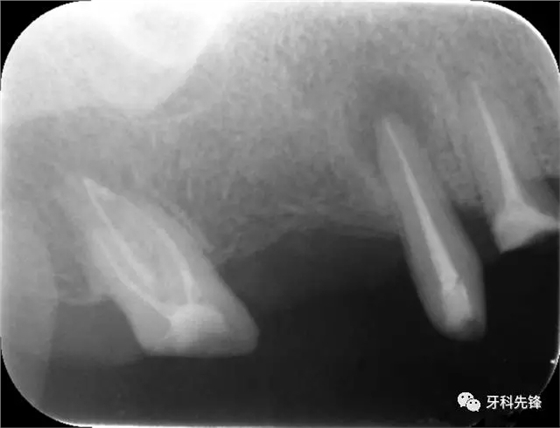

圖1術(shù)前X光片

640.webp.jpg

圖8治療術(shù)后X光片

640.webp (10).jpg